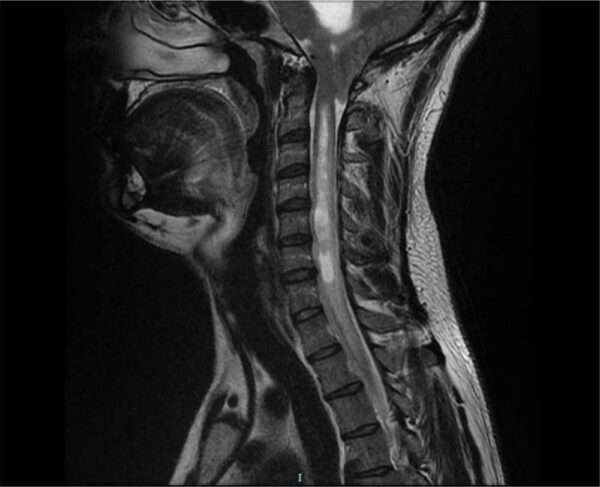

La resonancia magnética proporciona imágenes más detalladas y revela no solo la presencia de un siringe, o cavidad en la médula espinal, sino también los hallazgos característicos de la malformación de Arnold-Chiari. Entre estos hallazgos, se destaca el desplazamiento caudal del cuarto ventrículo, que es la estructura del sistema ventricular del cerebro que contiene líquido cefalorraquídeo. Este desplazamiento indica que las estructuras cerebrales están siendo empujadas hacia abajo debido a la falta de espacio en la fosa posterior.

La herniación de las amígdalas cerebelosas a través del foramen magno es otro hallazgo clave. Esta herniación puede resultar en la compresión de la médula espinal y el tronco encefálico, lo que lleva a síntomas neurológicos como dolores de cabeza, problemas de equilibrio, y alteraciones en la función motora y sensorial.

En pacientes con cavitación relacionada con lesiones pasadas o neoplasias intramedulares, se puede encontrar un aumento focal del diámetro de la médula espinal, que es observable a través de la mielografía o la resonancia magnética. Este aumento en el diámetro de la médula espinal sugiere la presencia de una cavidad que puede haber sido inducida por una lesión previa o por el crecimiento de un tumor dentro de la médula espinal. Estas cavidades pueden ser responsables de la disfunción neurológica observada, ya que interfieren con la transmisión de impulsos nerviosos a lo largo de la médula.